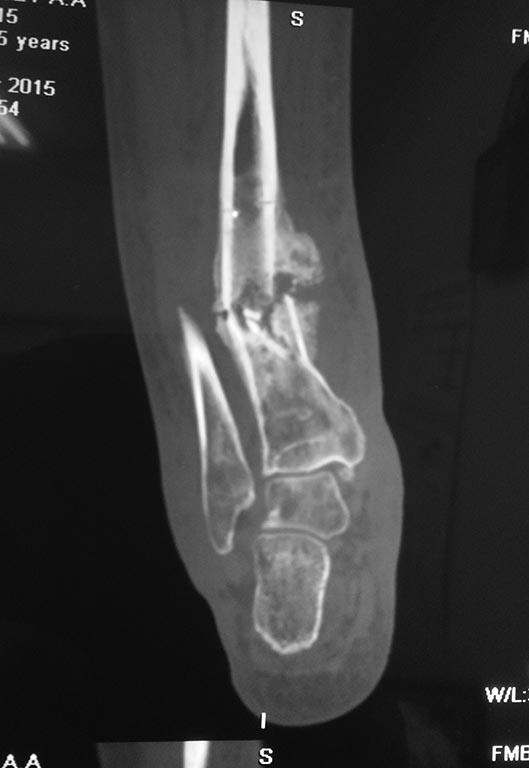

Небольшое уточнение: оперирован 1 августа, в ноябре снята база со стопы, в конце декабря демонтаж аппарата. Показания к снятию аппарата- заключение рентгенолога - консолидирующийся перелом, отсутствие патологической подвижности. Рана заживала около 3 -х месяцев условно первичным натяжением. Так как нет КТ руководствовались в основном рентген снимками.

Снимки при поступлении, спустя 2,5 месяца. Рентген снимки после снятия аппарата в архиве пришлю позже. Осылаю КТ от апреля.

У нас практически нет опыта лечения осложненных переломов. С учётом повреждения мягких тканей, избыточной костной мозоли очень хочется применить штифт( есть мнение что не хватило механики, а с биологией все хорошо). Ранняя нагрузка, нетравматичность более предпочтительней в данном случае? Там ещё не совсем ясно что с медиальной лодыжкой,на КТ Пишут что перелом не консолидированный. Возможно ли направить пациента на консультацию в пределах Москвы и МО кто занимается данной патологией?

костная аутопластика, МОС блокированной дистальной латеральной пластиной. На представленных снимках оценить консолидацию невозможно. Если же брать классические представления, то такой перелом не может срастись за 3-4 месяца, а бывает недостаточно и 6-12месяцев.

на мой взгляд, это гипертрофический тугой ложный сустав. Его можно лечить любым из перечисленных способов, каким лучше владеете: и аппаратом и ЗИМО и пластиной. А можно и консервативно попробовать по Сармиенто.